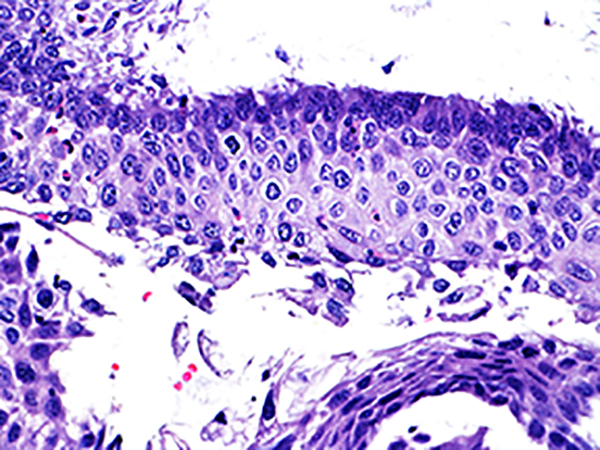

Case 5

Soft Bx CIN 1

40x - High Power